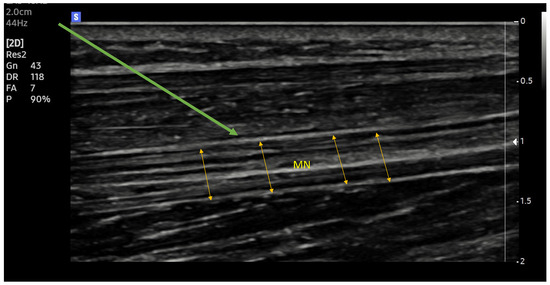

New ultrasound machines with digital image processing and customized image parameter settings make it easier to identify the selected structures (Figure 1 and Figure 2). Increasing the precision of delivery into the immediate vicinity of nerves increases the effectiveness of anaesthesia and makes it possible to reduce the dose of local anaesthetic drugs [33].

Figure 2.

Median nerve. Ultrasound longitudinal (long axes) view. MN (yellow arrows)—median nerve; Green arrow—needle trajectory; Arrowhead—extraneuronal needle placement.